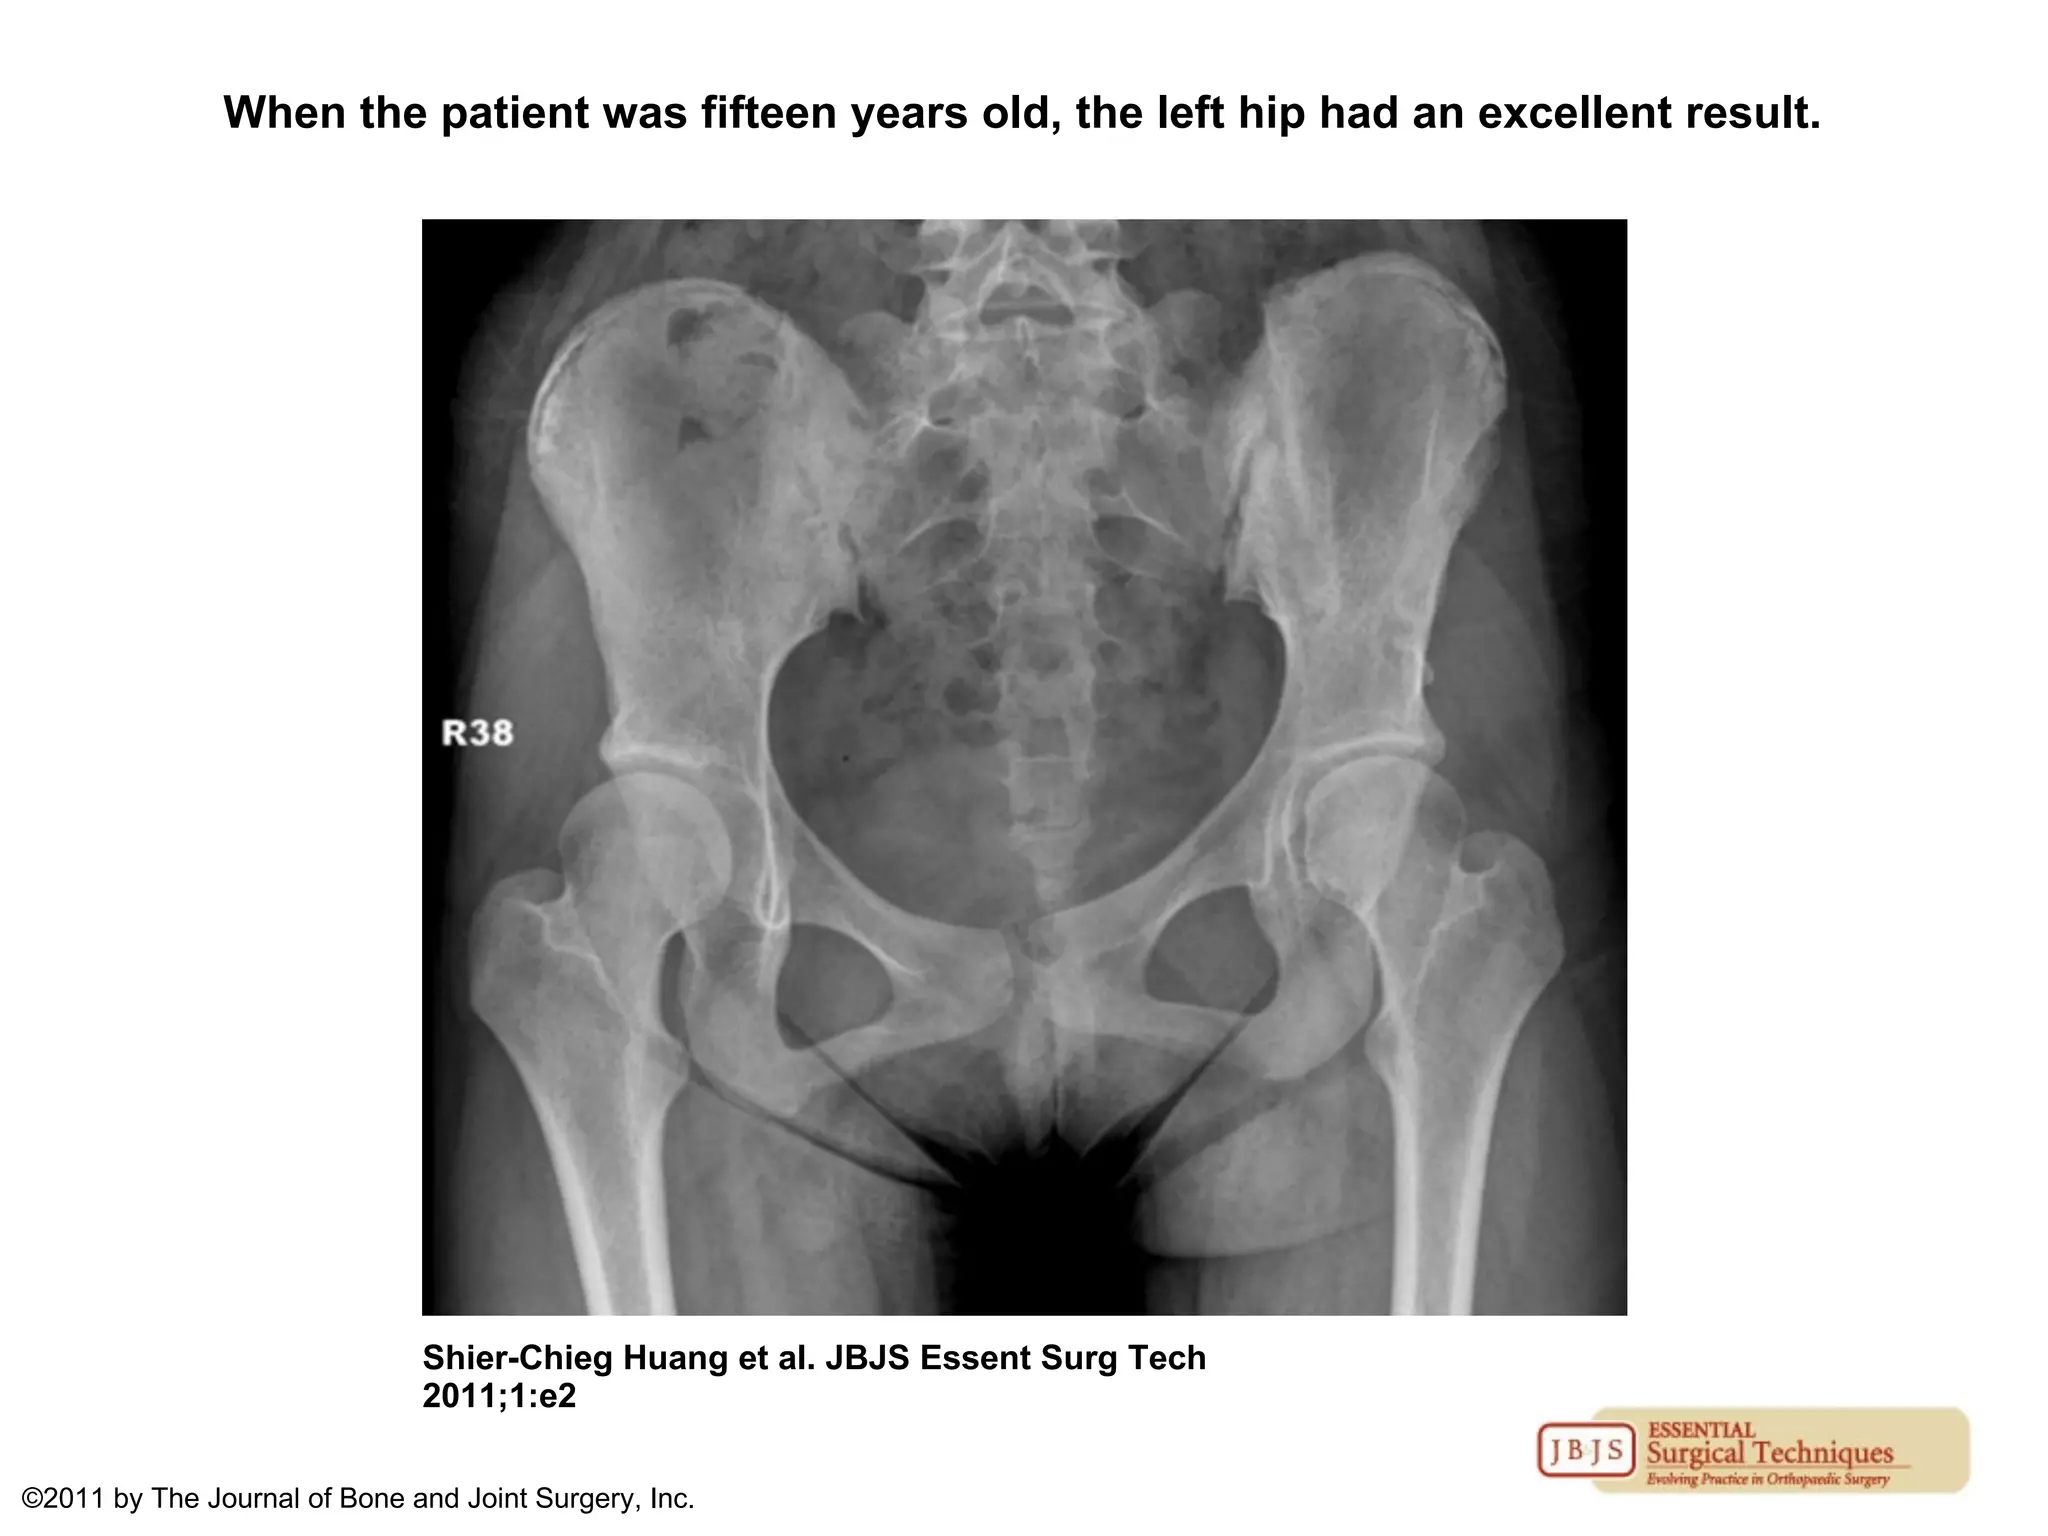

RESULTS

• If there was overcorrection or inferior

displacement of the reduced femoral head ,

there was a high risk of femoral head

osteonecrosis

• X rays of a patient treated at 20months

and followed up for 14yrs after the surgery

are shown

When the patient was fifteen years old, the left hip had an excellent result.

Shier-Chieg Huang et al. JBJS Essent Surg Tech

2011;1:e2

©2011 by The Journal of Bone and Joint Surgery, Inc.